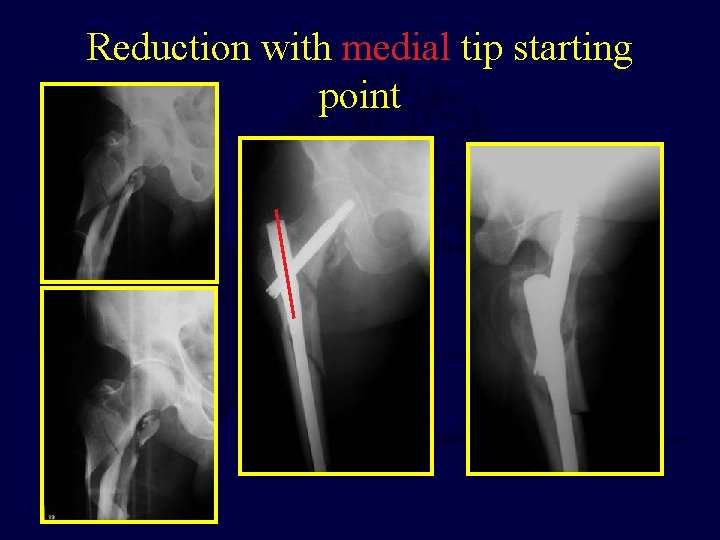

Reduction with medial tip starting point